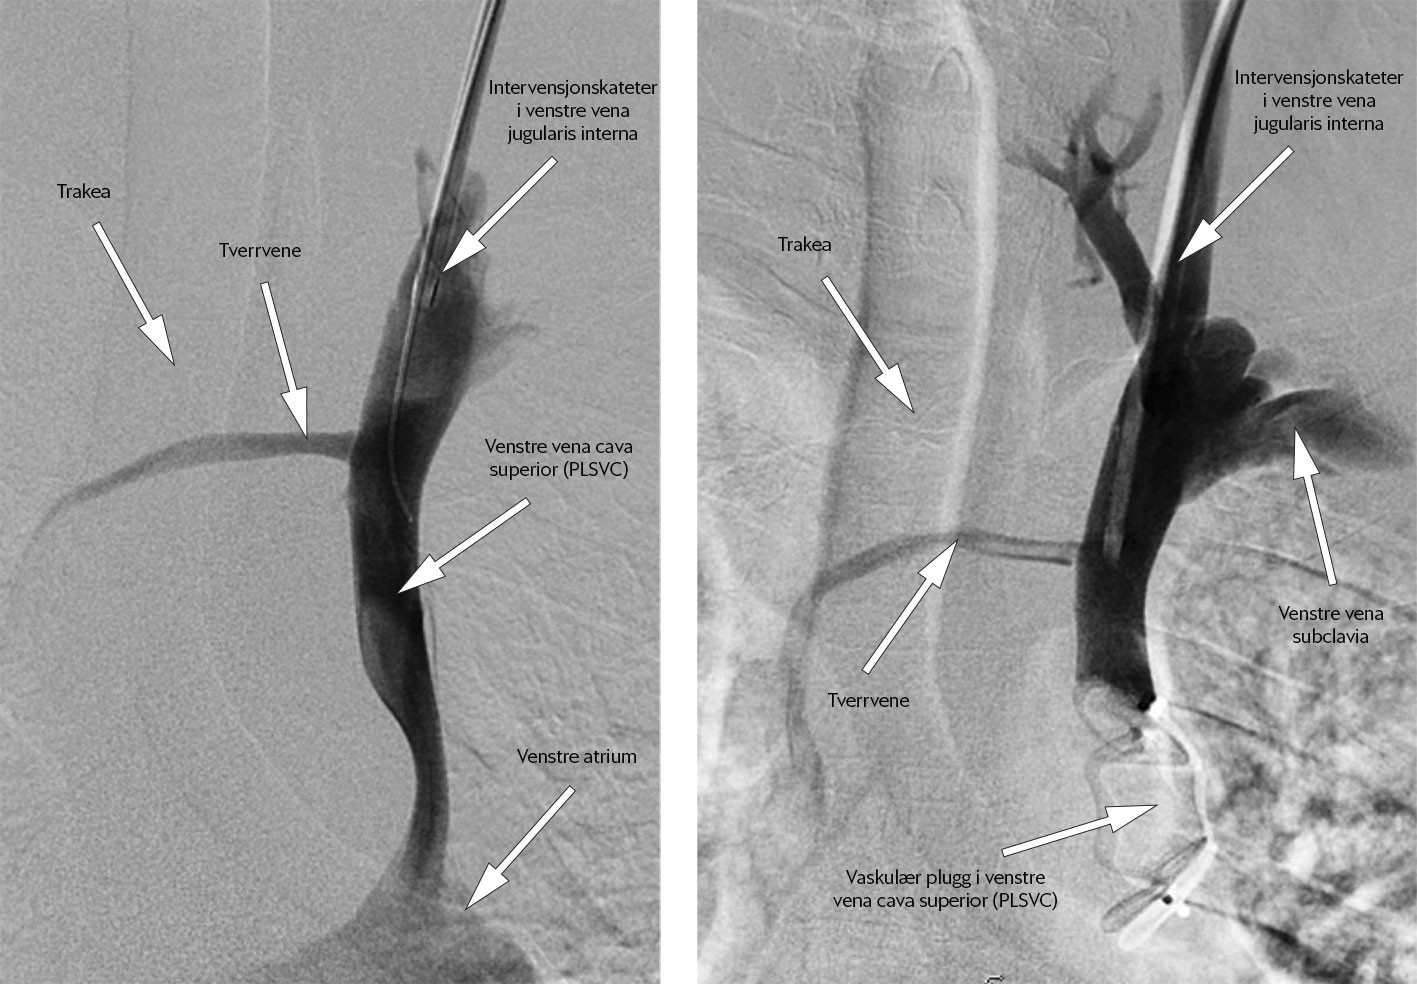

To dager senere sluttet kateteret å fungere, og pasienten fikk et nytt tilsvarende kateter via venstre overekstremitet. Prosedyren var ukomplisert, men kontroll-røntgen toraks viste unormalt leie av kateteret på venstre side av sternum (figur 2). CT toraks med intravenøs kontrast samme kveld viste at kateteret lå i en persisterende venstre vena cava superior, se figur 3a og figur 3b. Grunnet kontrastartefakter på bildene kunne man ikke da si sikkert om denne venen munnet ut i venstre eller høyre hjertehalvdel. Det gikk lett å aspirere blod og å injisere saltvann, og man tolket det som at kateteret fungerte normalt. Pasienten reiste hjem samme kveld i god form.

I samråd med kardiolog og infeksjonsmedisiner konkluderte man med persisterende venstre v. cava superior som årsak til pasientens to hjerneabscesser. Intravenøs antibiotika (ceftriakson 2 g × 2 og metronidazol 1 g × 1) ble kontinuert i åtte uker via høyresidige venetilganger. På grunn av alvorlig sykdomsforløp og fare for reinfeksjon fikk han profylakse med peroral amoksicillin 1 g × 3 fram til endelig behandling med lukking av persisterende venstre v. cava superior. Pasienten ble kurativt operert ved intervensjonsradiologisk avdeling på universitetssykehus tre måneder etter utskrivning fra nevrokirurgisk avdeling. Via tilgang i venstre v. jugularis interna ble det i lokalbedøvelse utført endovaskulær embolisering med plassering av en vaskulær plugg helt distalt i den persisterende venstre v. cava superior (figur 7). Forløpet var ukomplisert.